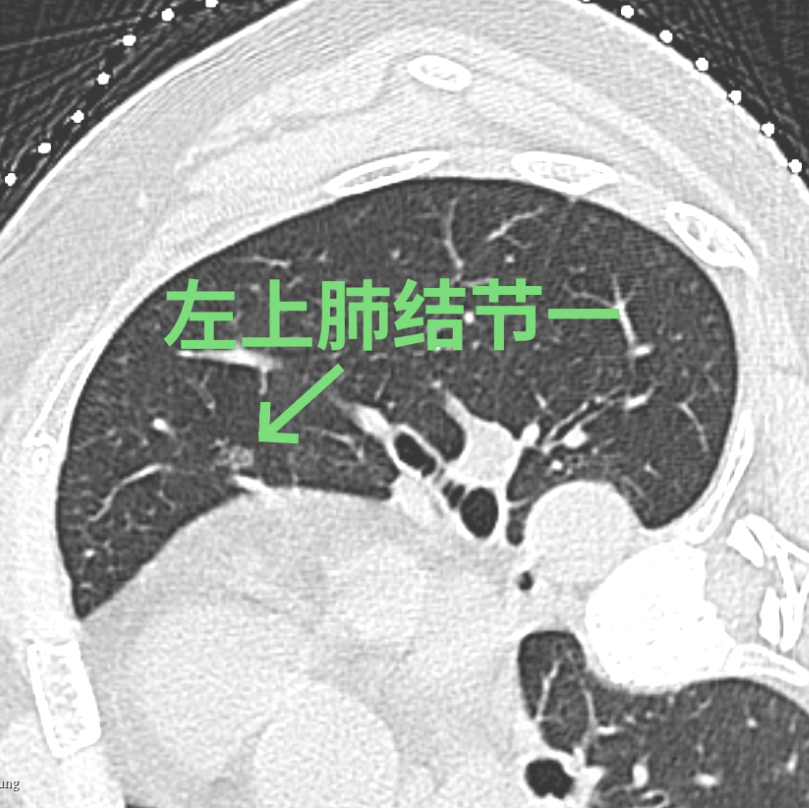

刘女士在体检时发现左肺有3个高危的磨玻璃结节,慕名找到我院胸部医学中心徐驯宇主任医师团队。在分析了刘女士的肺部影像资料后,徐驯宇发现刘女士左上肺的两个结节位置较浅表,其中一个结节最大径仅4.5mm,这类大小的结节在手术中不易定位;而左下肺的结节位置较深,如果全部采用手术切除的方法,将损失较多的正常肺组织,得不偿失。

经过徐驯宇主任医师、黄郴副主任医师和王捷阳医师的反复讨论,决定为刘女士实施杂交手术:首先由黄郴和王捷阳在CT引导下为刘女士左上肺的小结节打上金属钩作为标记,然后再对左下肺较深的结节进行热消融治疗;接着由徐驯宇主刀为刘女士进行胸腔镜下左上肺结节的切除。在术中,徐驯宇按照之前在CT引导下置入的金属钩,很快就定位到左上肺的磨玻璃结节,并进行精准的局部切除,整个过程仅耗时30分钟。术后的病理报告显示,这3个结节分别为两个原位癌和一个非典型腺瘤样增生。经过量身定制的杂交手术,刘女士顺利解除了肺部的3个健康隐患,3天就顺利恢复出院。

▲术中结节变化